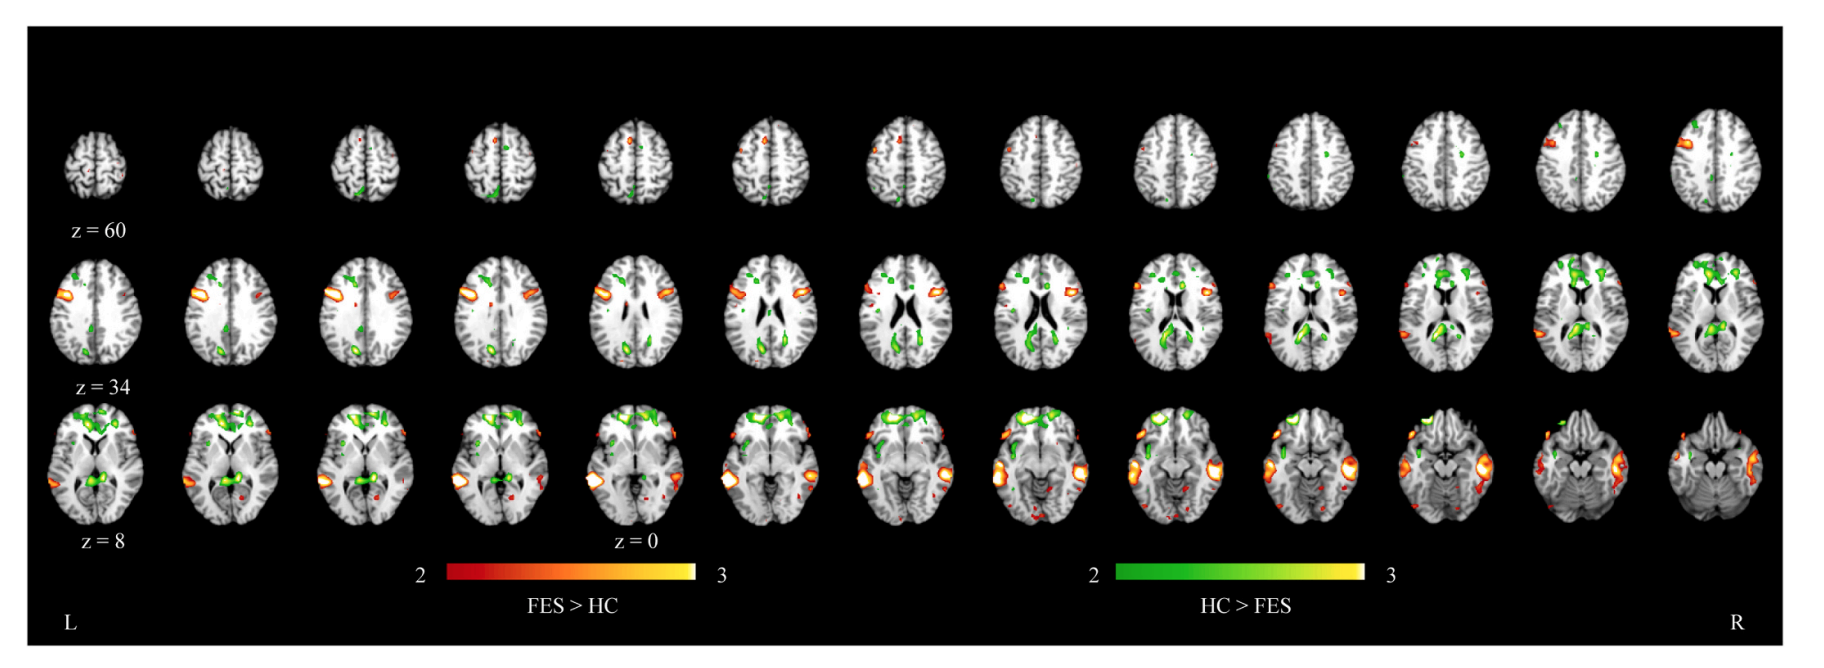

使用信號檢測論的數據分析方法表明:首發精神分裂癥患者幽默信號擊中率更低,并不能準確識別幽默信號。神經水平上,與健康對照組相比,首發精神分裂癥患者在腹側額中回和前扣帶回中的活動減弱,但在顳中回以及顳上回的活動增強。另外,在首發精神分裂癥患者中,腹側額中回與前扣帶回的腦活動與信號檢測論里的擊中率和判斷標準成正相關,而顳上回活動與判斷標準成正相關。

圖2. 首發精神分裂癥患者與健康對照組在幽默與非幽默條件對比中的神經活動差異

綜上所述,研究發現提示了首發精神分裂癥患者對幽默信號辨別力下降,與幽默加工缺損相關的額葉區域活動不足,以及顳葉區域活動過多。這些首發精神分裂癥患者幽默加工缺損背后的神經基礎可能是與該病癥相關的重要神經機制,可能是精神分裂癥譜系障礙群體潛在的干預靶標。而且,黃佳正在帶領團隊成員研發幽默認知訓練課程,打算用來考察認知干預提升精神分裂癥患者愉快體驗的效果,希望進一步理解精神障礙群體復雜社會認知缺損的原因。